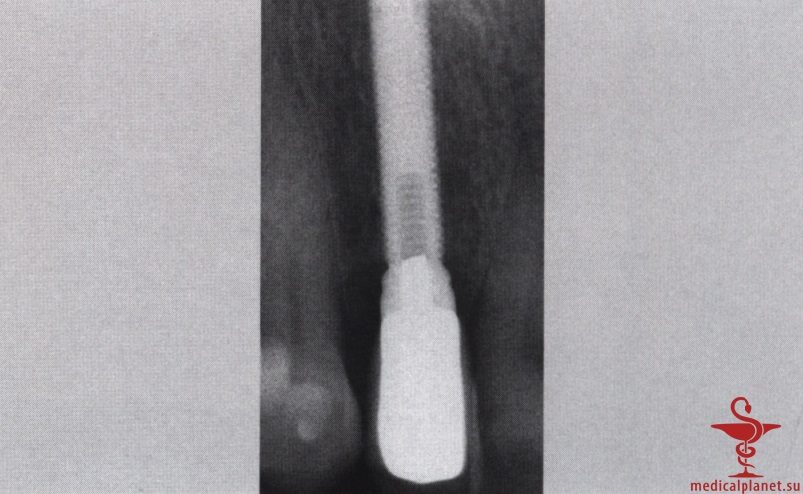

В частности, в эстетически значимой зоне имплантат не следует устанавливать в положении и направлении корня замещаемого зуба, поскольку в большинстве случаев это приведет к слишком вестибулярному положению и избыточному вестибулярному наклону имплантата. Обычно такая ситуация ассоциируется с выраженной рецессией десны, как это описывалось в отдельной статье на сайте (просим Вас пользоваться формой поиска по сайту выше) (рис. 1).

Кроме того, оказалось, что удаление зуба неизбежно сопровождается резорбцией альвеолярной кости, причем в большей степени с вестибулярной, чем с язычной стороны, а немедленная имплантация не позволяет предотвратить этот процесс. В передних отделах челюстей утрата вестибулярной кости часто приводит к неблагоприятному эстетическому результату. Сам факт отслаивания слизисто-надкостничного лоскута также усугубляет резорбцию костной ткани.